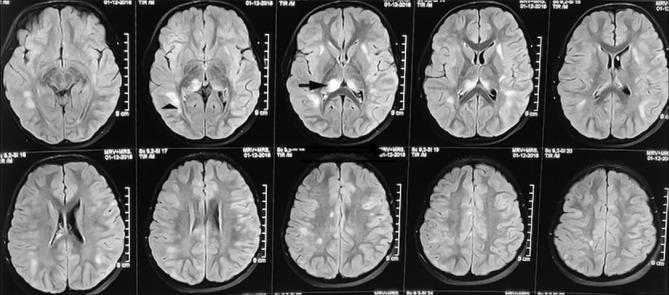

Roy Saheli, Joshi Nishigandha S, Ali Basit, Udani Vrajesh

Department of Pediatrics and Pediatric Neurology, P. D. Hinduja National Hospital and Medical Research Centre, Mumbai, Maharashtra, India.

Ann Indian Acad Neurol. 2025 Jul 1;28(4):611-614. doi: 10.4103/aian.aian_1019_24. Epub 2025 May 21.